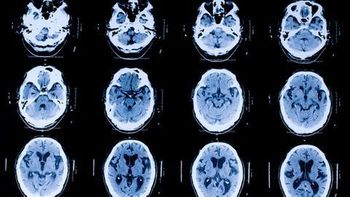

Software provides annotated and segmented brain images captured by Hyperfine’s portable MRI system.